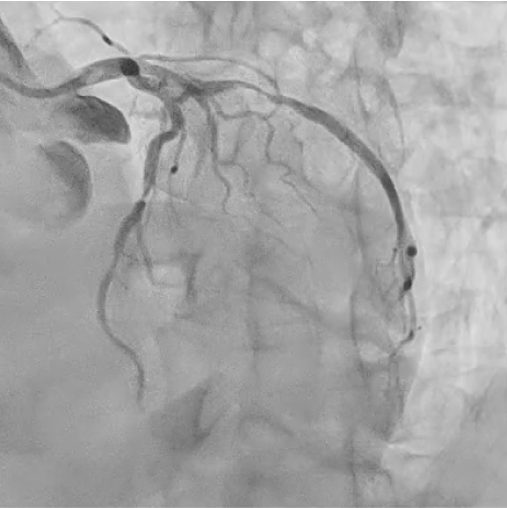

After the rupture, we replaced the inflator with one filled with undiluted contrast medium to improve pressure transmission. The balloon was then inflated at high pressure, which partially expanded the stent. Subsequently, we used a semi-compliant balloon for post-dilatation, achieving complete stent expansion without angiographic complications. Final angiography confirmed optimal stent deployment and TIMI 3 flow. The patient remained hemodynamically stable throughout the procedure and experienced no post-procedural complications.